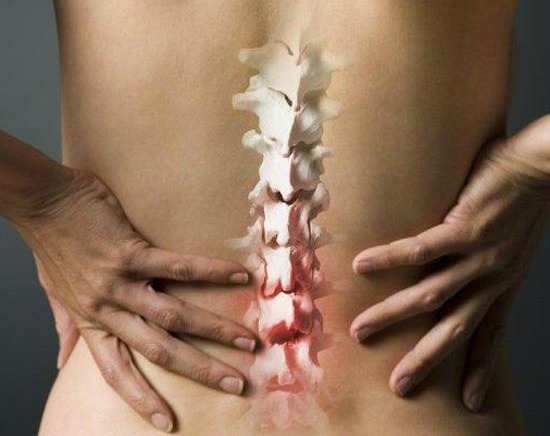

Ако ве мачат болки во зглобовите, имате чувство на “тежина” во нозете, стари повреди, итн.…